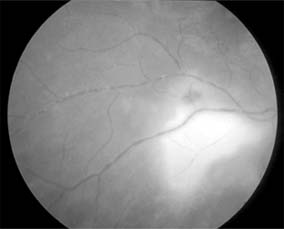

Central Retinal Vein Occlusion (new window  Figure 15-7)

Figure 15-7

Figure 15-7: Central retinal vein occlusion. Left: Photograph shows linear hemorrhages in the nerve fiber layer and punctate hemorrhages in the deeper retinal layers. Right: Fluorescein angiogram shows dilation of the veins.

Fundus examination shows dilated tortuous veins with retinal and macular edema, hemorrhages all over the posterior pole, and cotton-wool spots. The arterioles are usually attenuated, indicating generalized microvascular disease.

The prognosis for vision is poor. Fluorescein angiography demonstrates two types of response: a nonischemic type, with dilation of retinal vessels and edema; and an ischemic type, with large areas of capillary nonperfusion or evidence of retinal or anterior segment neovascularization. In 93% of ischemic and 50% of nonischemic central retinal vein occlusions, the ultimate visual acuity is less than 20/200.